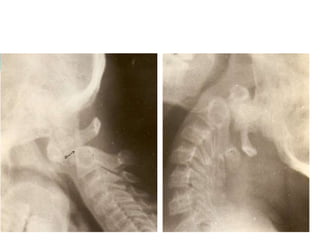

• Stress X-Rays (neutral, flexion, extention)

Radiological findings in 3 stages

• Stage I: Retropharyngeal abscess with ligamentous laxity +,

bony architecture of C1-C2 preserved.

• Stage II: Ligamentous disruption with AAD, minimal bone

destruction & retropharyngeal mass +

• Stage III: marked destruction of bone, complete obliteration

of anterior arch of C1 & complete loss of odontoid process,

marked AAD & O-A instability.